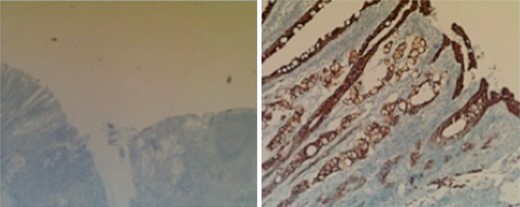

Subsequent surgical pathology results confirmed two separate malignant processes causing the carcinomatosis: Immunohistochemical examination was performed on the surgical specimens. The appendiceal tumor stained negative for CK-7 and positive for CK-20 (Fig. 1), whereas the ovarian sample stained positive for CK-7 and negative for CK-20 (Fig. 2), consistent with malignant processes of independent origins.